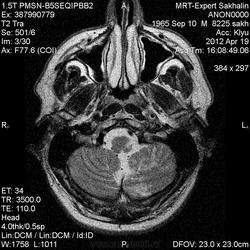

В анамнезе-21.03.2012 клиника геморрагического инсульта в бассейне ЗМА .Привезли с островов 5 дней назад.Провели КТ-в"в левых отделах моста гиподенсный очаг".Заключение :НМК по ишемическому типу, атрофия ствола мозга.Жалобы на головокружение,некоторую расторможенность.

У нас получились вот такие картинки ( контрастировать собрались завтра).По моему мнению, здесь не все укладывается в картину постишемических изменений.Буду рада все мнениям.Спасибо заранее.

Ишемическое повреждение левого полушария мозжечка, но общая картина мозга не здоровая, не было у пациента в прошлом травм или травмы в следствии ОНМК?

Спасибо, коллега!Вот и я про то же.+ еще в продолговатом мозге очаг в левых отделах.

а в мозжечке - не может быть глиома??? фибриллярная астроцитом??? пост-инсульт за месяц бы не так выглядел, на мой взгляд...

ОНМК по ишемическому типу в ВББ (басс.левой задней нижней мозжечковой артерии). ДВИ не делаете?

Я - за формирующиейся (практически сфомировавшиеся кистозно-глиозные) постишемические изменения в левой гемисфере мозжечка, ну и аналогичный очаг в стволе конечно же. На КТ эти изменения в остром периоде могли и не увидеть - из-за артефактов от костей основания черепа...

Смотрела снимки КТ-шные -кроме изменений в левых отделах продолговатого мозга ничего не насмотрела ( из меня плохой знаток КТ).

Na CT doljni biti vidni izmenenia i v mozjecike - ghipodensivnii ploho ocercionii uciastok. V stvole - bez somnenii posledstvia lakunarnogo insulita.